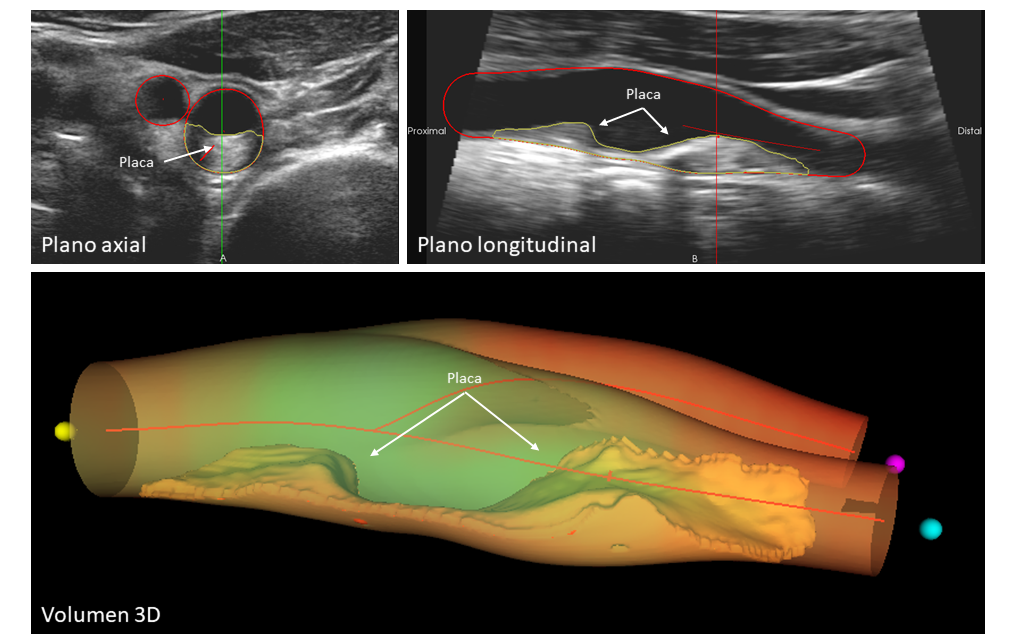

La imagen muestra un caso ejemplo de enfermedad ateroesclerótica que afecta a la arteria carótida. La vista axial (arriba a la izquierda) y longitudinal (arriba a la derecha) presentan una placa visible de gran tamaño y su extensión. La representación volumétrica en 3D (abajo) ofrece una visualización detallada y precisa de la placa, lo que permite una evaluación completa y exhaustiva de la enfermedad.

En el presente estudio, señala la doctora Ana García Álvarez, co-primera firmante, investigadora en CNIC y jefa de servicio de cardiología en el Hospital Clinic Barcelona, los participantes fueron examinados con tecnología de imagen -ecografía vascular, técnica que permite visualizar en detalle el interior de los vasos sanguíneos- para cuantificar la carga de placa carotídea, y con tomografía computarizada para evaluar la calcificación de las arterias coronarias.

“La placa carotídea es una acumulación de colesterol, calcio y otras sustancias presentes en la sangre que se deposita en las paredes de la arteria -aclara la doctora García Álvarez-. Cuando estas placas se forman, pueden estrechar o bloquear las arterias carótidas, reduciendo el flujo sanguíneo al cerebro y aumentando el riesgo de eventos cardiovasculares graves, como el accidente cerebrovascular o ictus”.